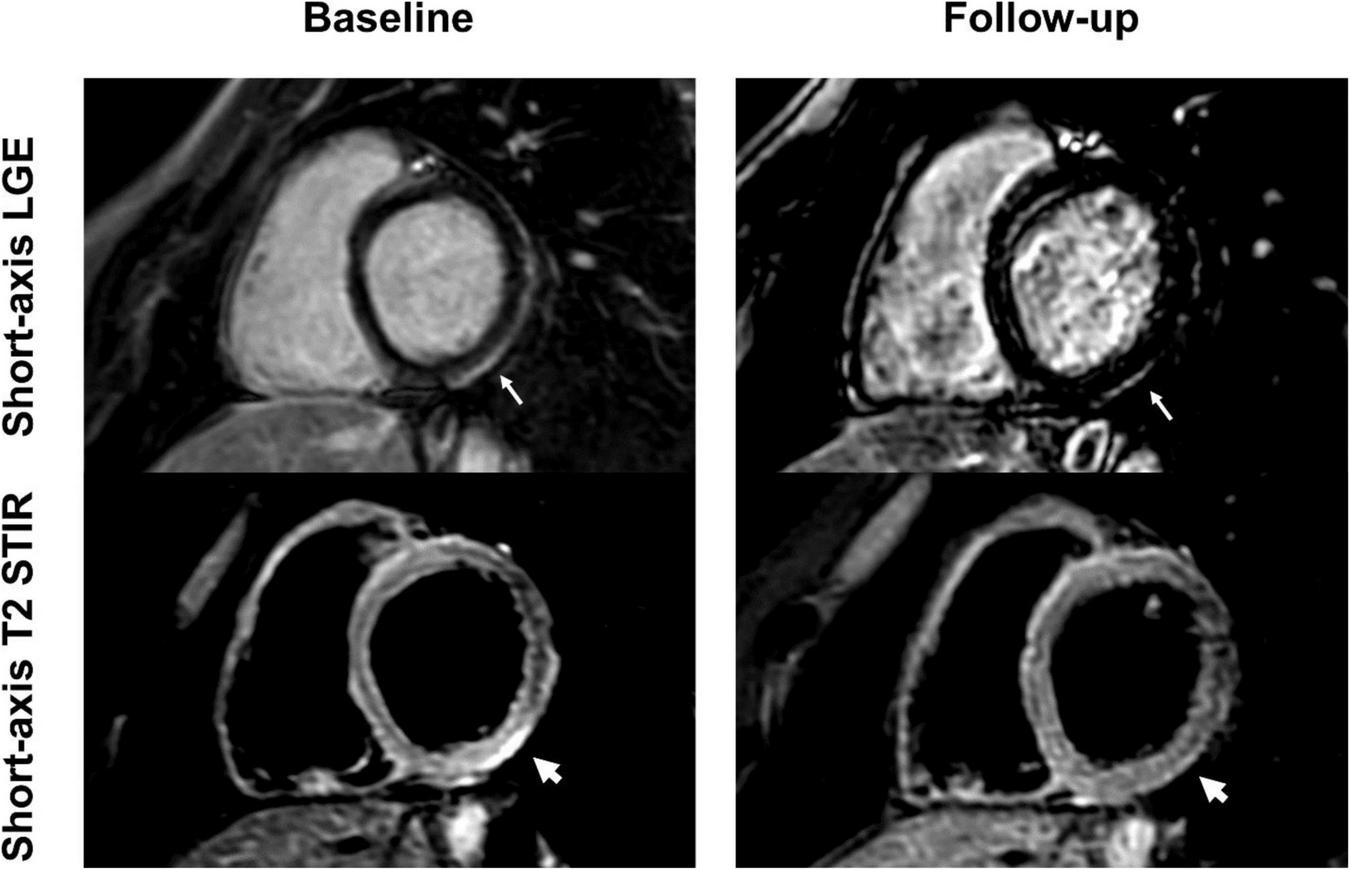

FIGURE 2

Baseline and follow-up cardiac imaging in a 25-year-old male with acute vaccine associated myocarditis after receiving his second vaccine with Pfizer/BioNTech. Short-axis and 4-chamber late gadolinium enhancement (LGE) views demonstrate subepicardial enhancement along the midventricular and apical inferolateral wall (arrows). T2 short-axis short tau inversion recovery (STIR) imaging corresponding to the LGE findings shows a resolution of edema from baseline to follow-up (arrow). Normalization of T1 and T2 relaxation times are also demonstrated over time (arrow). Note, however, the persistent LGE along the inferolateral wall even at follow-up, consistent with scar tissue.

FIGURE 6

Short-axis late gadolinium enhancement (LGE) and short-axis T2 short tau inversion recovery (STIR) views of a 24-year-old, previously healthy male after receiving the second dose of the Pfizer/BioNTech vaccine. LGE at the basal inferolateral wall (thin arrows) shows a marked decrease at 6-month follow-up, with only minimal remaining findings. T2 STIR imaging shows focal myocardial edema corresponding to the location of the LGE (thick arrows) with complete resolution at follow-up. The patient reported complete resolution of previous clinical symptoms but complained of new onset exertional dyspnea.